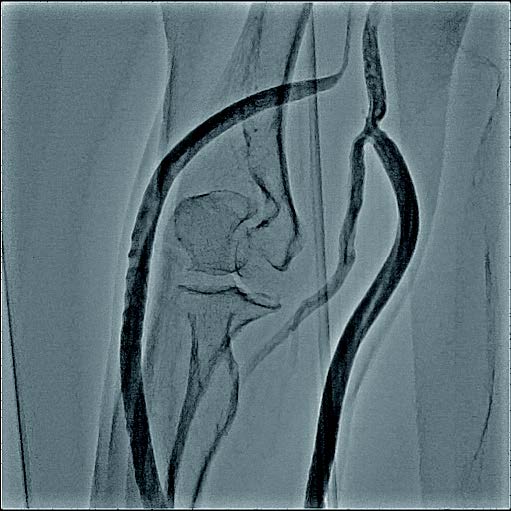

実際の治療

バイアバーン® ステントグラフト留置の手技については、当施設では概ね毎回同じ手技を実施している。ステントグラフトの長さについては病変に依存するが、径については6 mmの人工血管に対して、7 mmのバイアバーン® ステントグラフトを留置している。

静脈とはいえ、透析患者においては硬化性変化が強い病変が多く、indentation を残さずに pre dilatation をかけておくことが重要と考えられる。そこで、径7 mmのバイアバーン® ステントグラフト留置前に、径6 mmの高耐圧バルーンにてしっかり拡張し、indentationを残さないことを確認した。バイアバーン® ステントグラフト留置後もバルーンでステント内、特に人工血管とのオーバーラップ部位にしっかり圧をかけて後拡張を行っている。

また、バイアバーン® ステントグラフトは、位置決めをした後の留置時に移動する事象は自施設で行った症例ではほとんど認めていないが、展開時のstabilityを保つため0.018 inchのサポートワイヤーを用いることが多い。当患者においても、上記手技を行い良好なinitial successを得られた。他症例もほぼ同一の手技で行っているがサイズなどで問題になった症例は、本稿の執筆時点では経験していない。